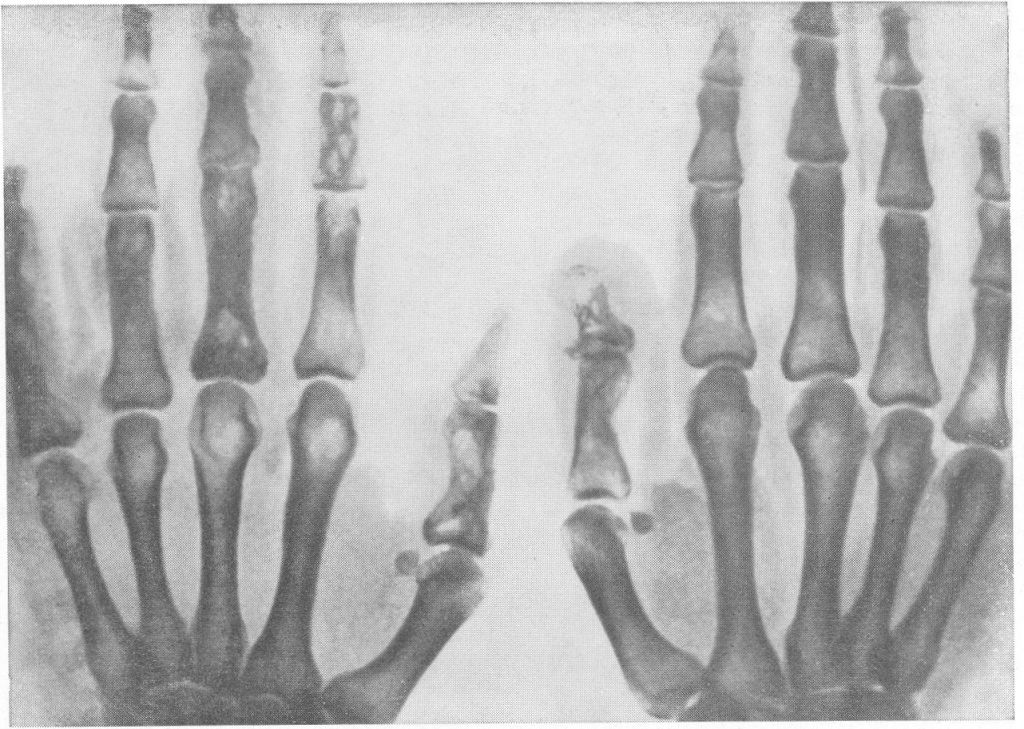

Deformirleýji osteoartroz. podagra

Süňk we bogun inçekeseli.

Süňk skeletinden geçýän keseller